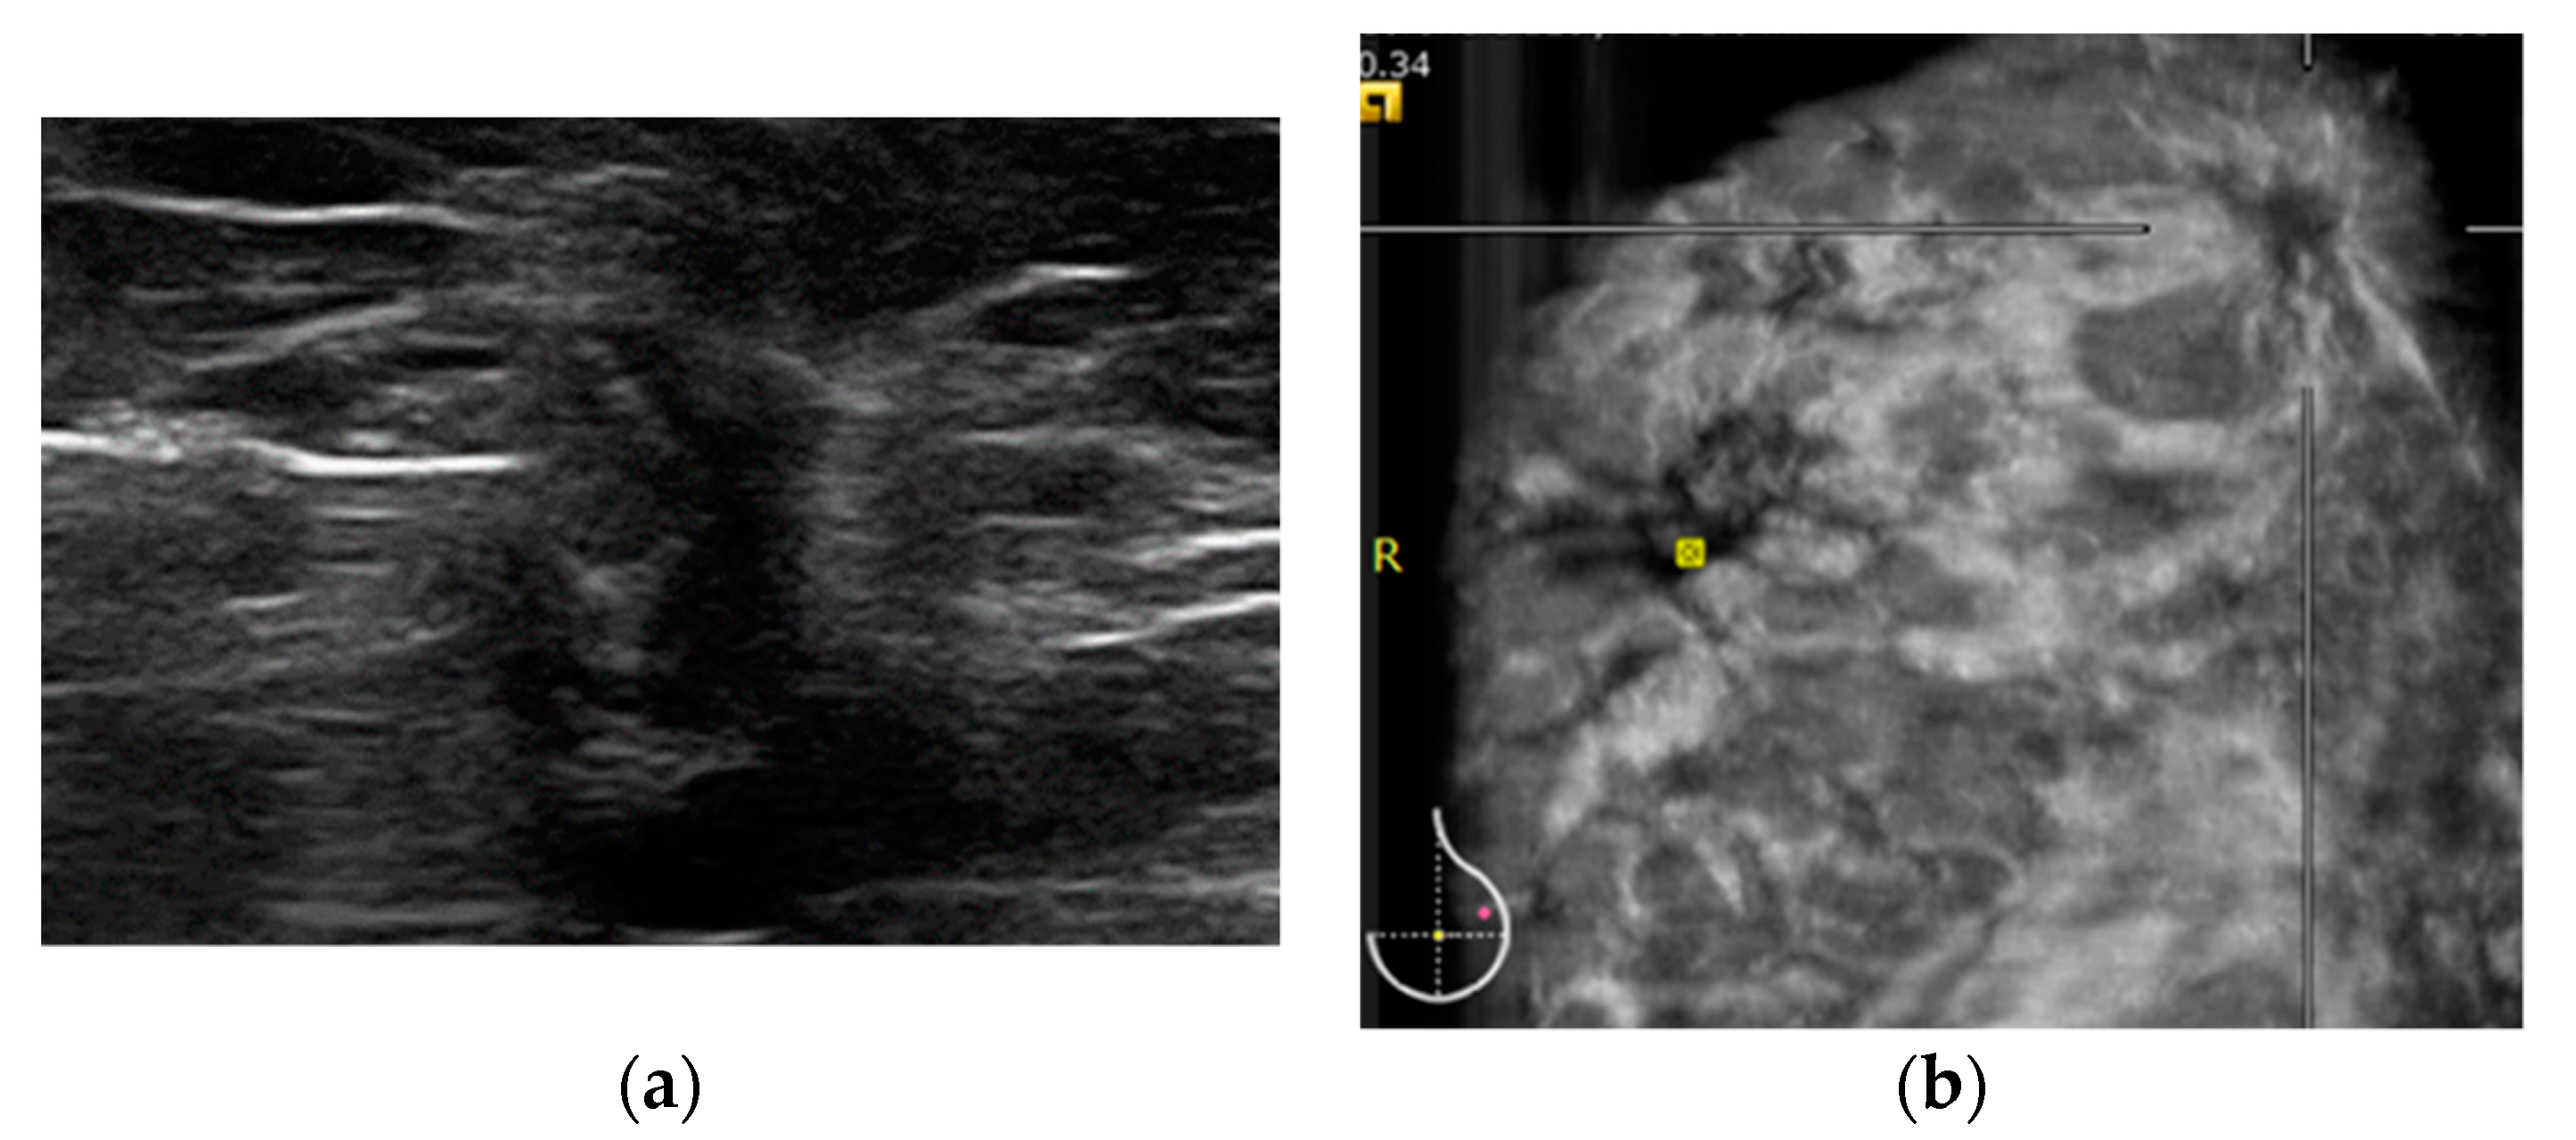

2.2. HHUS Examination

2.3. ABVS Execution

2.4. ABVS Interpretation